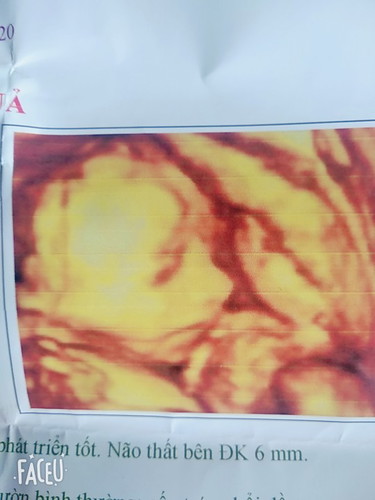

Chuột tháng 7 của mẹ

Bạn chuột có mũi đẹp thế

Mũi bé cao quá😊

Mũi em cưng quá 😙